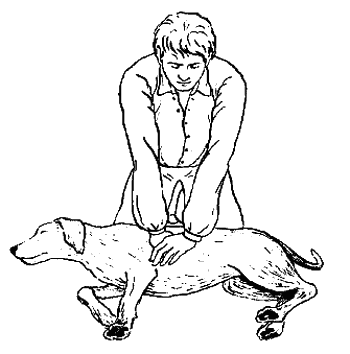

Непрямой массаж сердца

Для собаки, находящейся без сознания, важно обеспечить условия, способствующие нормальному притоку крови к головному мозгу для обеспечения его клеток кислородом. Для этого можно поднять животное за задние конечности вниз головой, если собака маленькая.

Крупное животное нужно положить на ровную поверхность вниз головой.

Транспортировка собаки с повреждением позвоночника